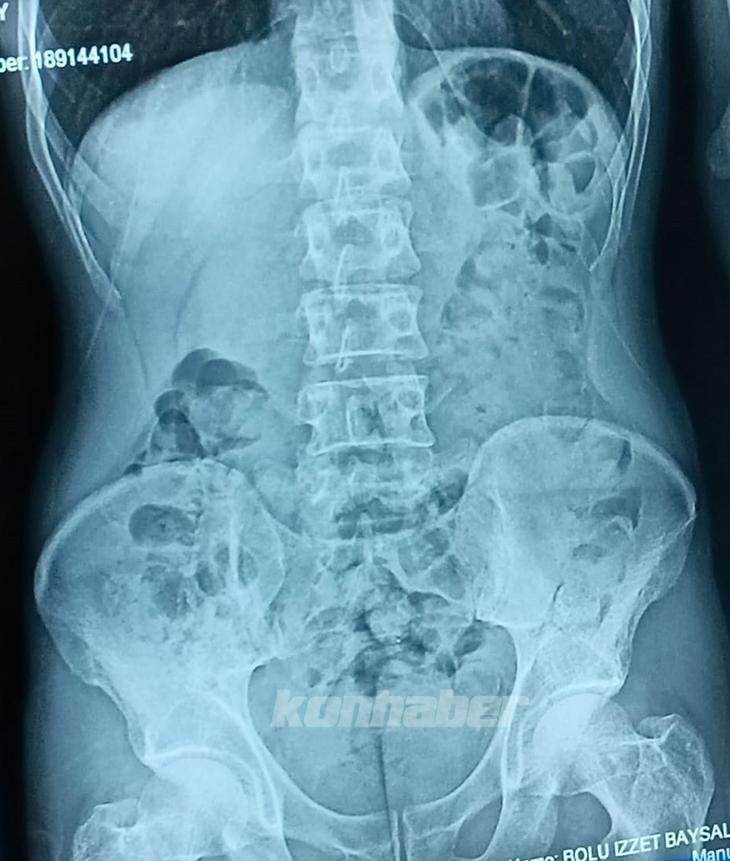

Edinilen bilgiye göre, İl Emniyet Müdürlüğü Narkotik Suçlarla Mücadele Şube Müdürlüğü ekipleri, doğu illerinden İstanbul’a seyir halinde olan yolcu otobüsünde uyuşturucu madde taşındığı ihbarı üzerine çalışma başlattı. Ekipler, il sınırına girdiği tespit edilen yolcu otobüsünü uygulama noktasında durdurdu. Otobüste bulunan yolculardan Şefik B.’nin eliyle karnını tuttuğu ve şüpheli hareketleri olduğunu gören ekipler, şahsı olay yerinde sorguladı. Yapılan sorgusunda midesinde kapsül halinde uyuşturucu madde olduğunu itiraf eden Şefik B., hastaneye götürülerek mide röntgeni çekildi. Röntgende midesinde çok sayıda kapsül tespit edilen Şefik B.’nin, 48 parça halinde 542 gram eroini doğal yollarla çıkarması sağlandı.